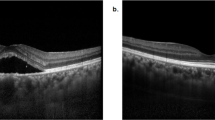

Subretinal fluid is a risk factor for growth and malignant transformation of choroidal naevi, however it is unclear if this applies to subclinical fluid that is only detectable by optical coherence tomography (OCT). The objective of this study was to determine the prevalence and associations of subclinical but OCT-detectable subretinal fluid over choroidal naevi.

Of 309 identified consecutive cases, the mean patient age was 65 years, 89.3% of patients were Caucasian and 3.9% were Asian. The prevalence of subclinical but OCT-detectable subretinal fluid associated with choroidal naevi was 11.7% (36/309). Naevi with fluid were associated with larger basal diameters, greater thickness, presence of a halo, orange pigmentation, hyperautofluorescence, and hypodensity on B-scan ultrasonography.

Of choroidal naevi where subretinal fluid is not visible on clinical examination, 11.7% demonstrate subretinal fluid on OCT scans. These naevi more commonly exhibit features known to be associated with growth and transformation to melanoma. The presence of subclinical OCT-detectable fluid over choroidal naevi may assist in their risk stratification.